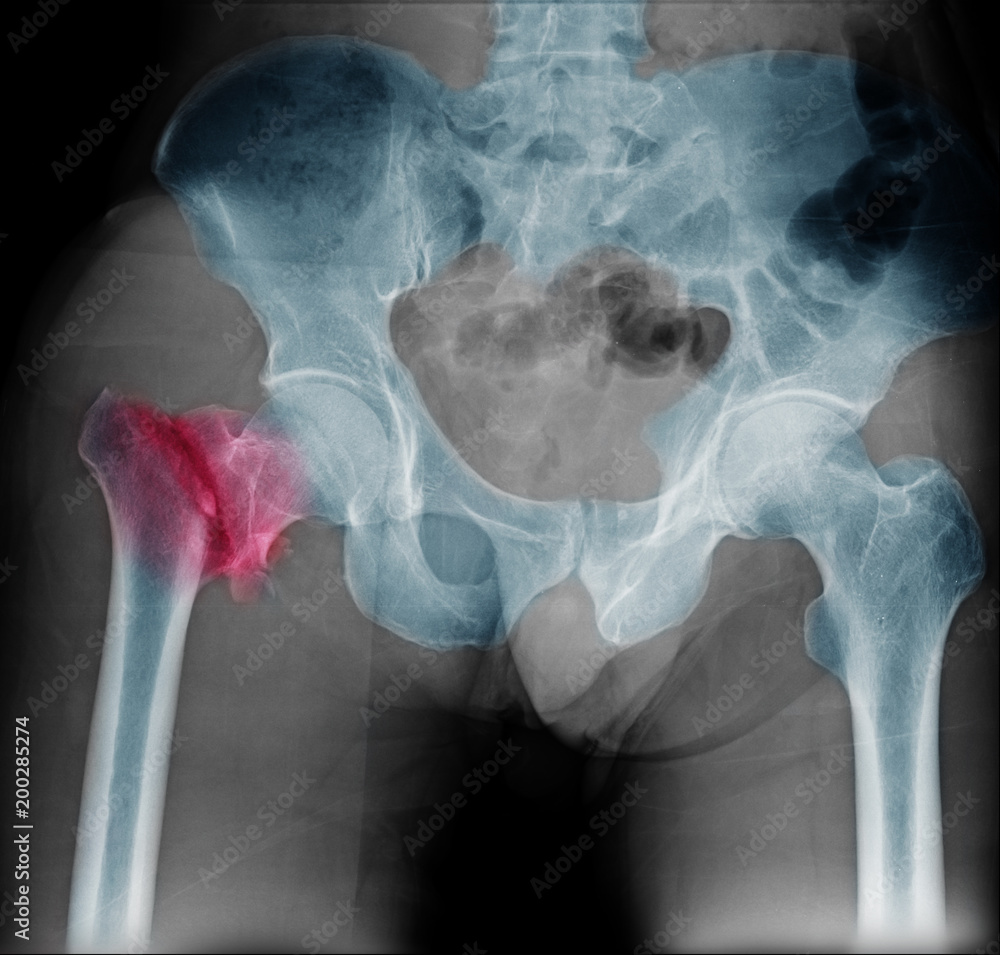

Hip Fracture X-Ray . Radiographs of the hip, radiographs of the pelvis, or radiographs of the pelvis and hips is usually. The majority of hip fractures can be diagnosed on plain film radiographs. A femoral neck fracture occurs one to two inches from the hip joint. These fractures are common among older adults and can be related to osteoporosis. The most common types of hip fractures are: This topic will review the major types of hip fractures, including basic anatomy, fracture classification, and clinical and radiographic. They tend to occur in older patients, and in those who have osteoporosis. Proximal femoral fractures are a subset of fractures that occur in the hip region. An anteroposterior view of the pelvis should be obtained along with a lateral view of the affected hip.